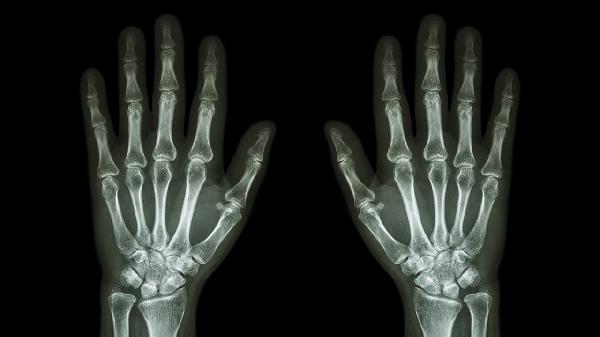

服用附桂骨痛片期间应忌食生冷、油腻食物,避免饮酒。孕妇、阴虚火旺者禁用,过敏体质者慎用。关节疼痛急性发作或持续加重时,应及时就医完善X线、风湿四项等检查。长期服药者需定期复查肝肾功能,用药过程中出现恶心、皮疹等不适需立即停药并就诊。日常注意关节保暖,可进行游泳、太极拳等低强度运动以维持关节活动度。